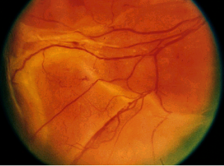

视网膜内微血管异常(IRMA)

视网膜内微血管异常(IRMA)是扭曲扩展的视网膜内血管片段。

视网膜上的点状微血管瘤和视网膜表面清晰可见的新生血管都不属于视网膜内微血管异常。

▲ 视网膜内微血管异常(A)

▲ 视网膜内微血管异常(B)